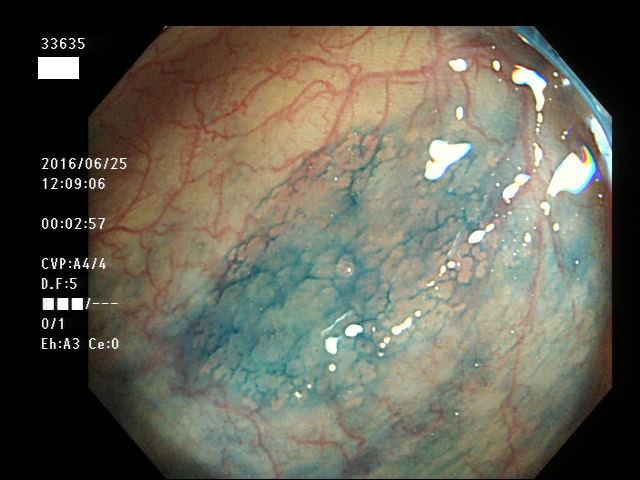

上記100名より抽出した平坦・陥凹型腺腫(=癌化の危険が高いが見落としやすい病変)の内視鏡写真